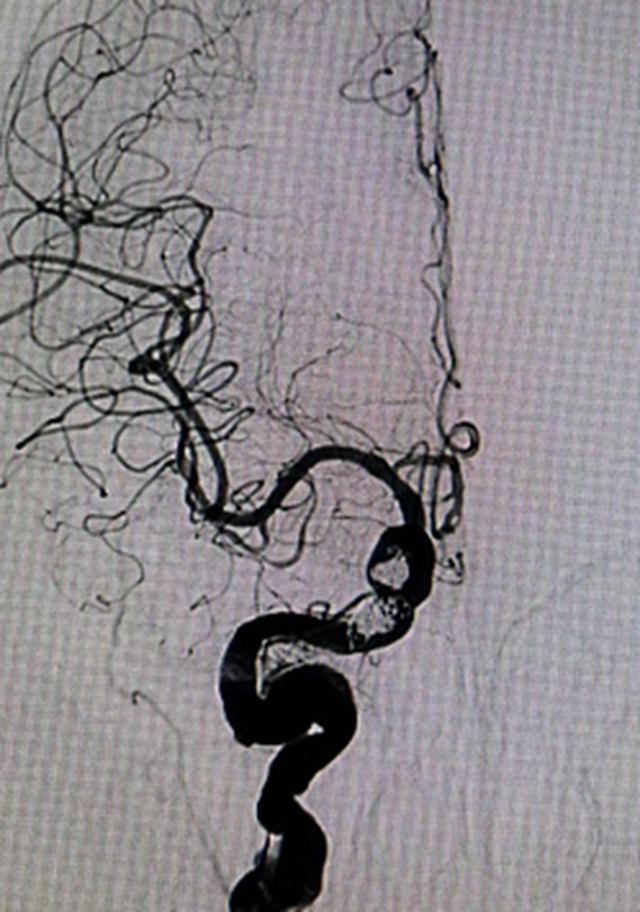

术后造影图片

考虑到患者病情迅速进行性加重的特殊性,在请示医院及科室领导后,黄昌仁教授带领团队根据疫情防控要求完善了相关术前准备,急诊在局部麻醉下,医生们先使用三维造影找到瘘口和引流静脉。随后,使用微导丝导引微导管进入眼静脉和岩下窦共同瘘口处,利用弹簧圈栓塞共同瘘口,再在球囊辅助下,使用胶水彻底栓塞颈动脉侧瘘口。栓塞后,工作角度造影显示瘘口消失,颈动脉通畅;栓塞后正侧位造影显示瘘口完全消失,大脑前动脉恢复血流,异常引流静脉消失。